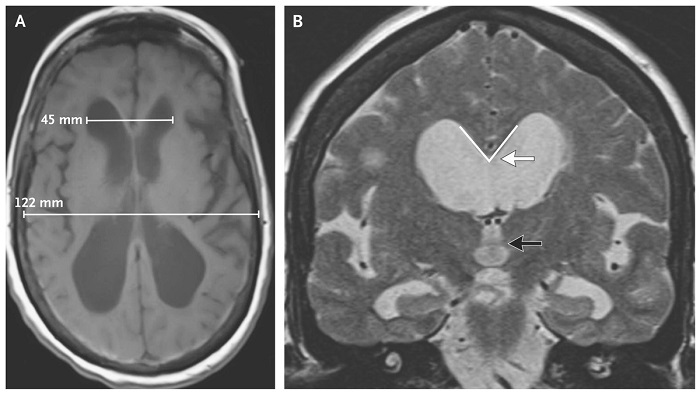

Salah satu tanda utama hidrosefalus pada bayi adalah pembesaran kepala yang cepat, juga di kenal sebagai makrosefalus. Sehingga kepala yang membesar di sebabkan oleh penumpukan cairan dalam rongga otak yang menyebabkan tulang tengkorak bayi belum menyatu sepenuhnya. Meskipun dapat menimbulkan tantangan serius bagi individu yang terkena. Tetapi penelitian dan pengembangan terus berlangsung untuk meningkatkan diagnosis dan pengobatan. Biasanya diagnosis Penyakit Hydrocephalus sering melibatkan pencitraan otak menggunakan teknik seperti ultrasound, CT scan atau MRI.

Penyakit Hydrocephalus Kondisi Medis Yang Kompleks Di Tandai Oleh Penumpukan Cairan Di Otak, yang dapat menyebabkan tekanan yang berlebihan dan pembesaran pada kepala bayi atau anak. Penyebab dari kondisi ini dapat bervariasi dan seringkali melibatkan berbagai faktor yang kompleks. Salah satu penyebab utamanya adalah ketidakseimbangan antara produksi dan resorpsi cairan serebrospinal (CSF). CSF adalah cairan yang di produksi di dalam otak dan berfungsi untuk melindungi dan menyokong jaringan otak. Ketika produksi CSF berlebihan atau aliran normalnya terganggu, misalnya oleh penyumbatan saluran CSF, maka cairan dapat menumpuk di dalam otak.